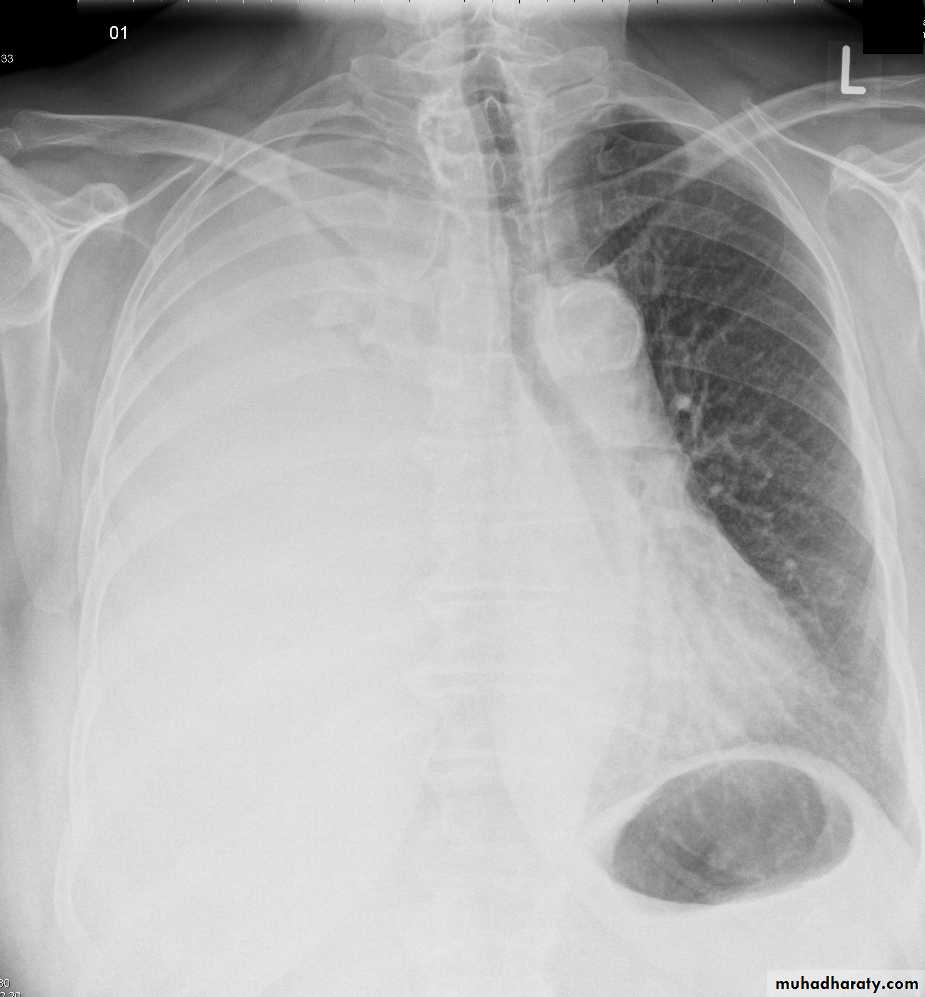

Chest imaging -2Pleural effusionPleural effusion tends to be used as a catch-all term denoting a collection of fluid within the pleural space. This can be further divided into exudates and transudates depending on the biochemical analysis of aspirated pleural fluid. Essentially it represents any pathological process which overwhelms the pleura's ability to reabsorb fluid.

Radiographic appearances

Plain radiograph

Chest radiographs are the most commonly used examination to assess for presence of a pleural effusion, however it should be noted that on a routine erect chest x-ray as much as 250-600 ml of fluid is required before it becomes evident 6. A lateral decubitus film is most sensitive, able to identify even a small amount of fluid. At the other extreme, supine films can mask large quantities of fluid.

Both PA and AP erect films are insensitive to small amounts of fluid. Features include:

blunting of the costophrenic angle

blunting of the cardiophrenic angle

fluid within the horizontal or oblique fissures

eventually a meniscus will be seen, on frontal films seen laterally and gently sloping medially

A subpulmonic effusion (infrapulmonary effusion) may be seen when there is previously established pulmonary disease, but can also be encountered in normal lungs , They are more common on the right, and usually unilateral

with large volume effusions, mediastinal shift occurs away from the effusion (note: if coexistent collapse dominates then mediastinal shift may occur towards the effusion)